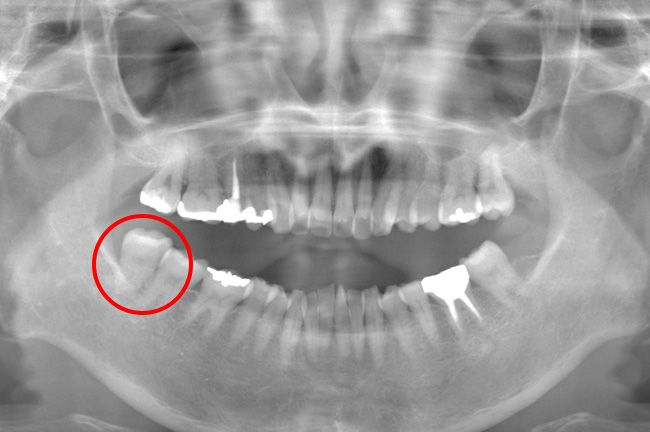

CASE 7

根が曲がっているため抜歯をする事が出来ないと他院で言われていた親知らずでしたが事前にCT撮影を行い形状と神経との位置関係を確認して抜歯を行いました。麻酔をしてから抜くまで30分ほどでした。痛み出血もほとんどありませんでした。

抜歯前

抜歯後

基本情報

| 年齢・性別 | 40代・女性 |

|---|---|

| 主訴 | 右下8/頬を噛んでしまうため右下親知らずを抜きたい |

| 治療内容 | 通常抜歯 |

| 治療期間 | 約30分 |

| 治療費 | 約3,000円 |

| リスク・副作用 | 2〜3日は腫れと痛みがある。 |